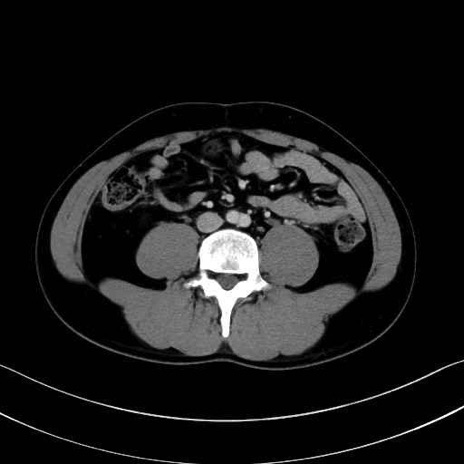

中殿筋 (Gluteus medius)